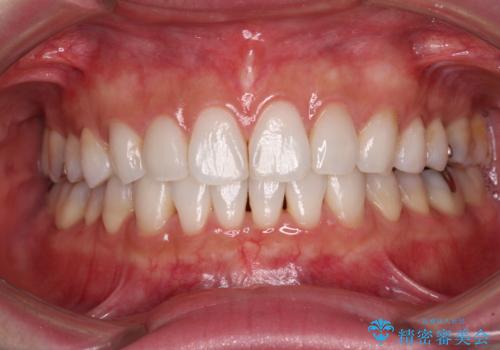

みるみる歯並びが整っていったため、「しっかりと毎日22時間以上装着できるのだろうか」という患者様自身が抱いていた不安も払拭されました。

口元を見られているという視線を気にすることなく笑えるようになり、患者様には大変満足していただきました。